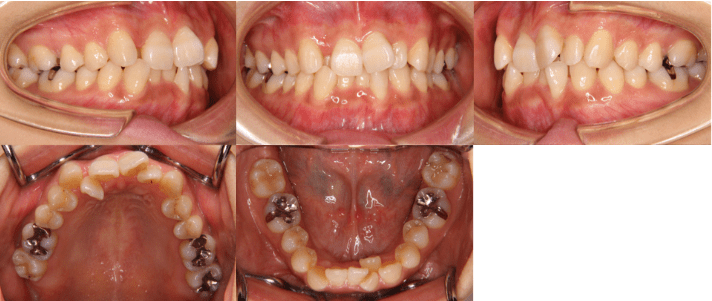

<治療前>

<治療後>

• 初診時年齢:25歳7ヶ月

• 主訴:前歯のガタガタ

• 診断:交叉咬合を伴う叢生症例

• 治療内容:小臼歯4本を抜歯した後、インビザラインを使用して主訴である叢生の改善を行いました。

• 治療期間:2年

• リスク:矯正治療による歯の移動に伴う痛み、歯根吸収、虫歯

• 費用:80万円